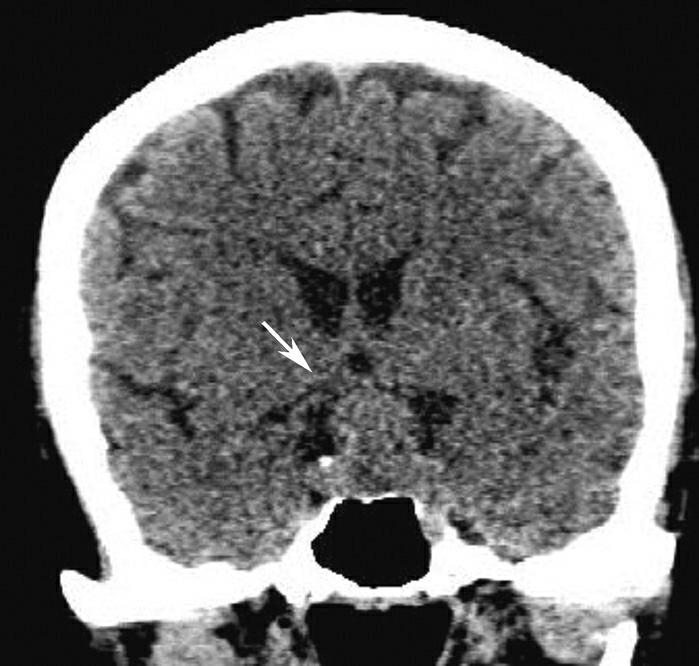

蝶鞍两侧为海绵窦,其内包含颈内动脉及第Ⅲ~Ⅵ对脑神经。海绵窦的密度升高或体积增大常提示病变存在。海绵窦外侧为颞叶,两者之间隔以海绵窦外侧壁。鞍背后方为桥前池及其后方的脑桥,桥前池内可见基底动脉断面,呈圆形稍高密度影。层面中部两侧为颞骨乳突部,其内气化的骨性腔隙为乳突气房。脑桥后方为第四脑室,呈半圆形或新月形,小脑半球的病变(如肿瘤、炎症、出血等)常压迫第四脑室,导致其变形甚至闭塞(图1-2-13)。两侧小脑半球间为小脑蚓部。小脑半球与颞骨乳突部间可见乙状窦。小脑蚓部后方为直窦与上矢状窦汇入窦汇处,窦汇两侧为横窦。静脉窦血栓时可见上述静脉窦增宽、密度明显升高(图1-2-14)。

图1-2-14 静脉窦增宽、密度升高(静脉窦血栓)

男,47岁,头痛2周,意识模糊2天,无头颅外伤史。A.CT平扫示双侧横窦增宽、密度增高(黑箭),提示静脉窦血栓;B.MRI T 1 WI提示双侧乙状窦、横窦血栓形成(白箭)